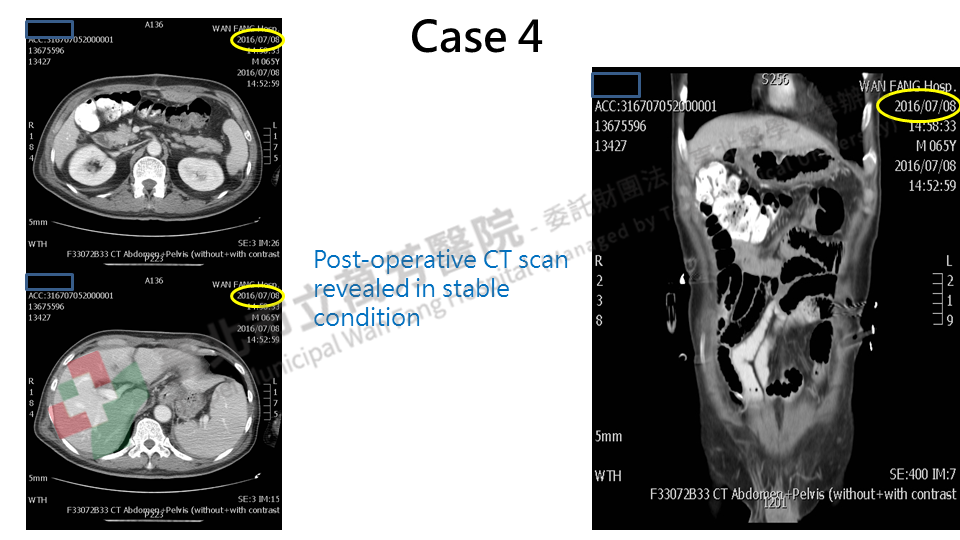

Case 4: A recurrent colon cancer. This patient received colon cancer surgery at 2011 at other hospital with pathological stage IIIa, and adjuvant chemotherapy. Intraperitoneal recurrence was noted at 2014 December, then systemic chemotherapy with target therapy for 12 cycles, but the result was poor, so another 6 cycles were added. However, the disease progressed then another target therapy was given at 2015. However, the treatment was not completed due to side effects of target therapy, and the cancer metastasized to lung. Later, the patient consulted us. After detailed evaluation at Wan-Fang Hospital, we performed total parietal peritonectomy, cytoreduction surgery, resection of the lung lesion and HIPEC. The post-operative condition was very well.